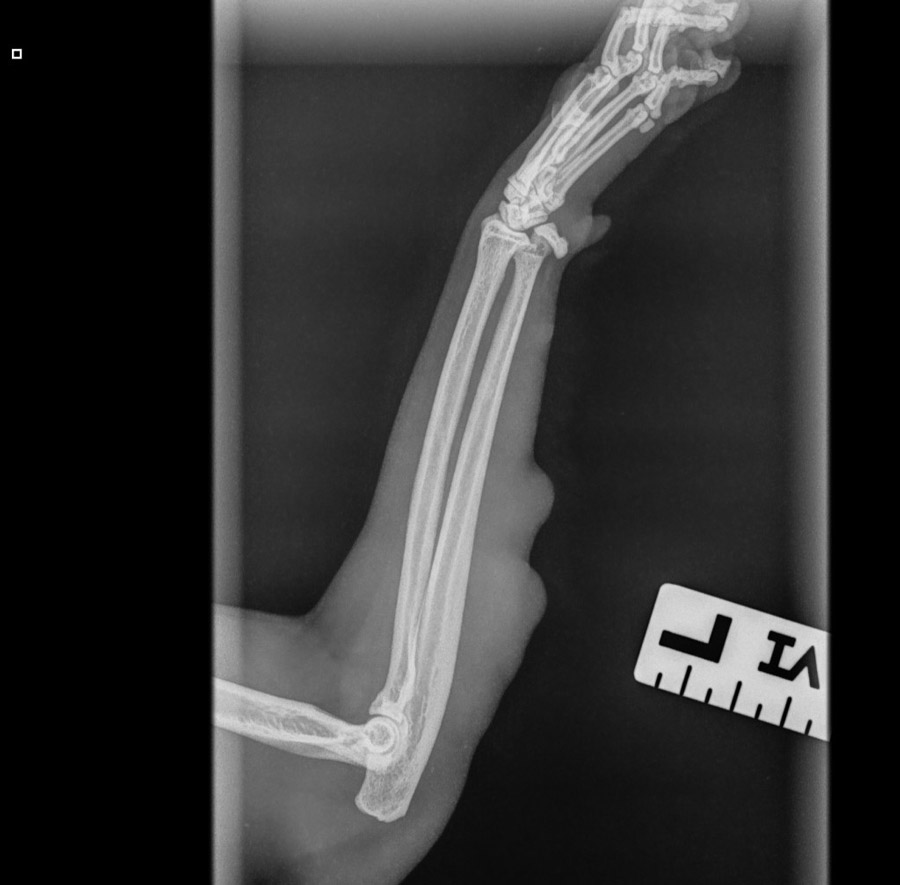

Niin, eli patti tosiaan tuli takaisin. Tänään käytiin Mörrin kanssa lääkärillä. Lääkärinä toimi Evidensia Nekalan Virpi Arminen, joka on ihan huipputyyppi ja varsinkin kirurgina todella loistava. Hän teki Mörrin ensimmäisenkin kasvaimen poisto-operaation ja PESUn eläinten kanssa ollaan käytetty hänen palveluitaan paljon. Kasvain on kasvanut etujalan lihakseen pituudelta kiinni. Jalasta otettiin röntgenkuvat, joissa selvisi että luihin … Read more